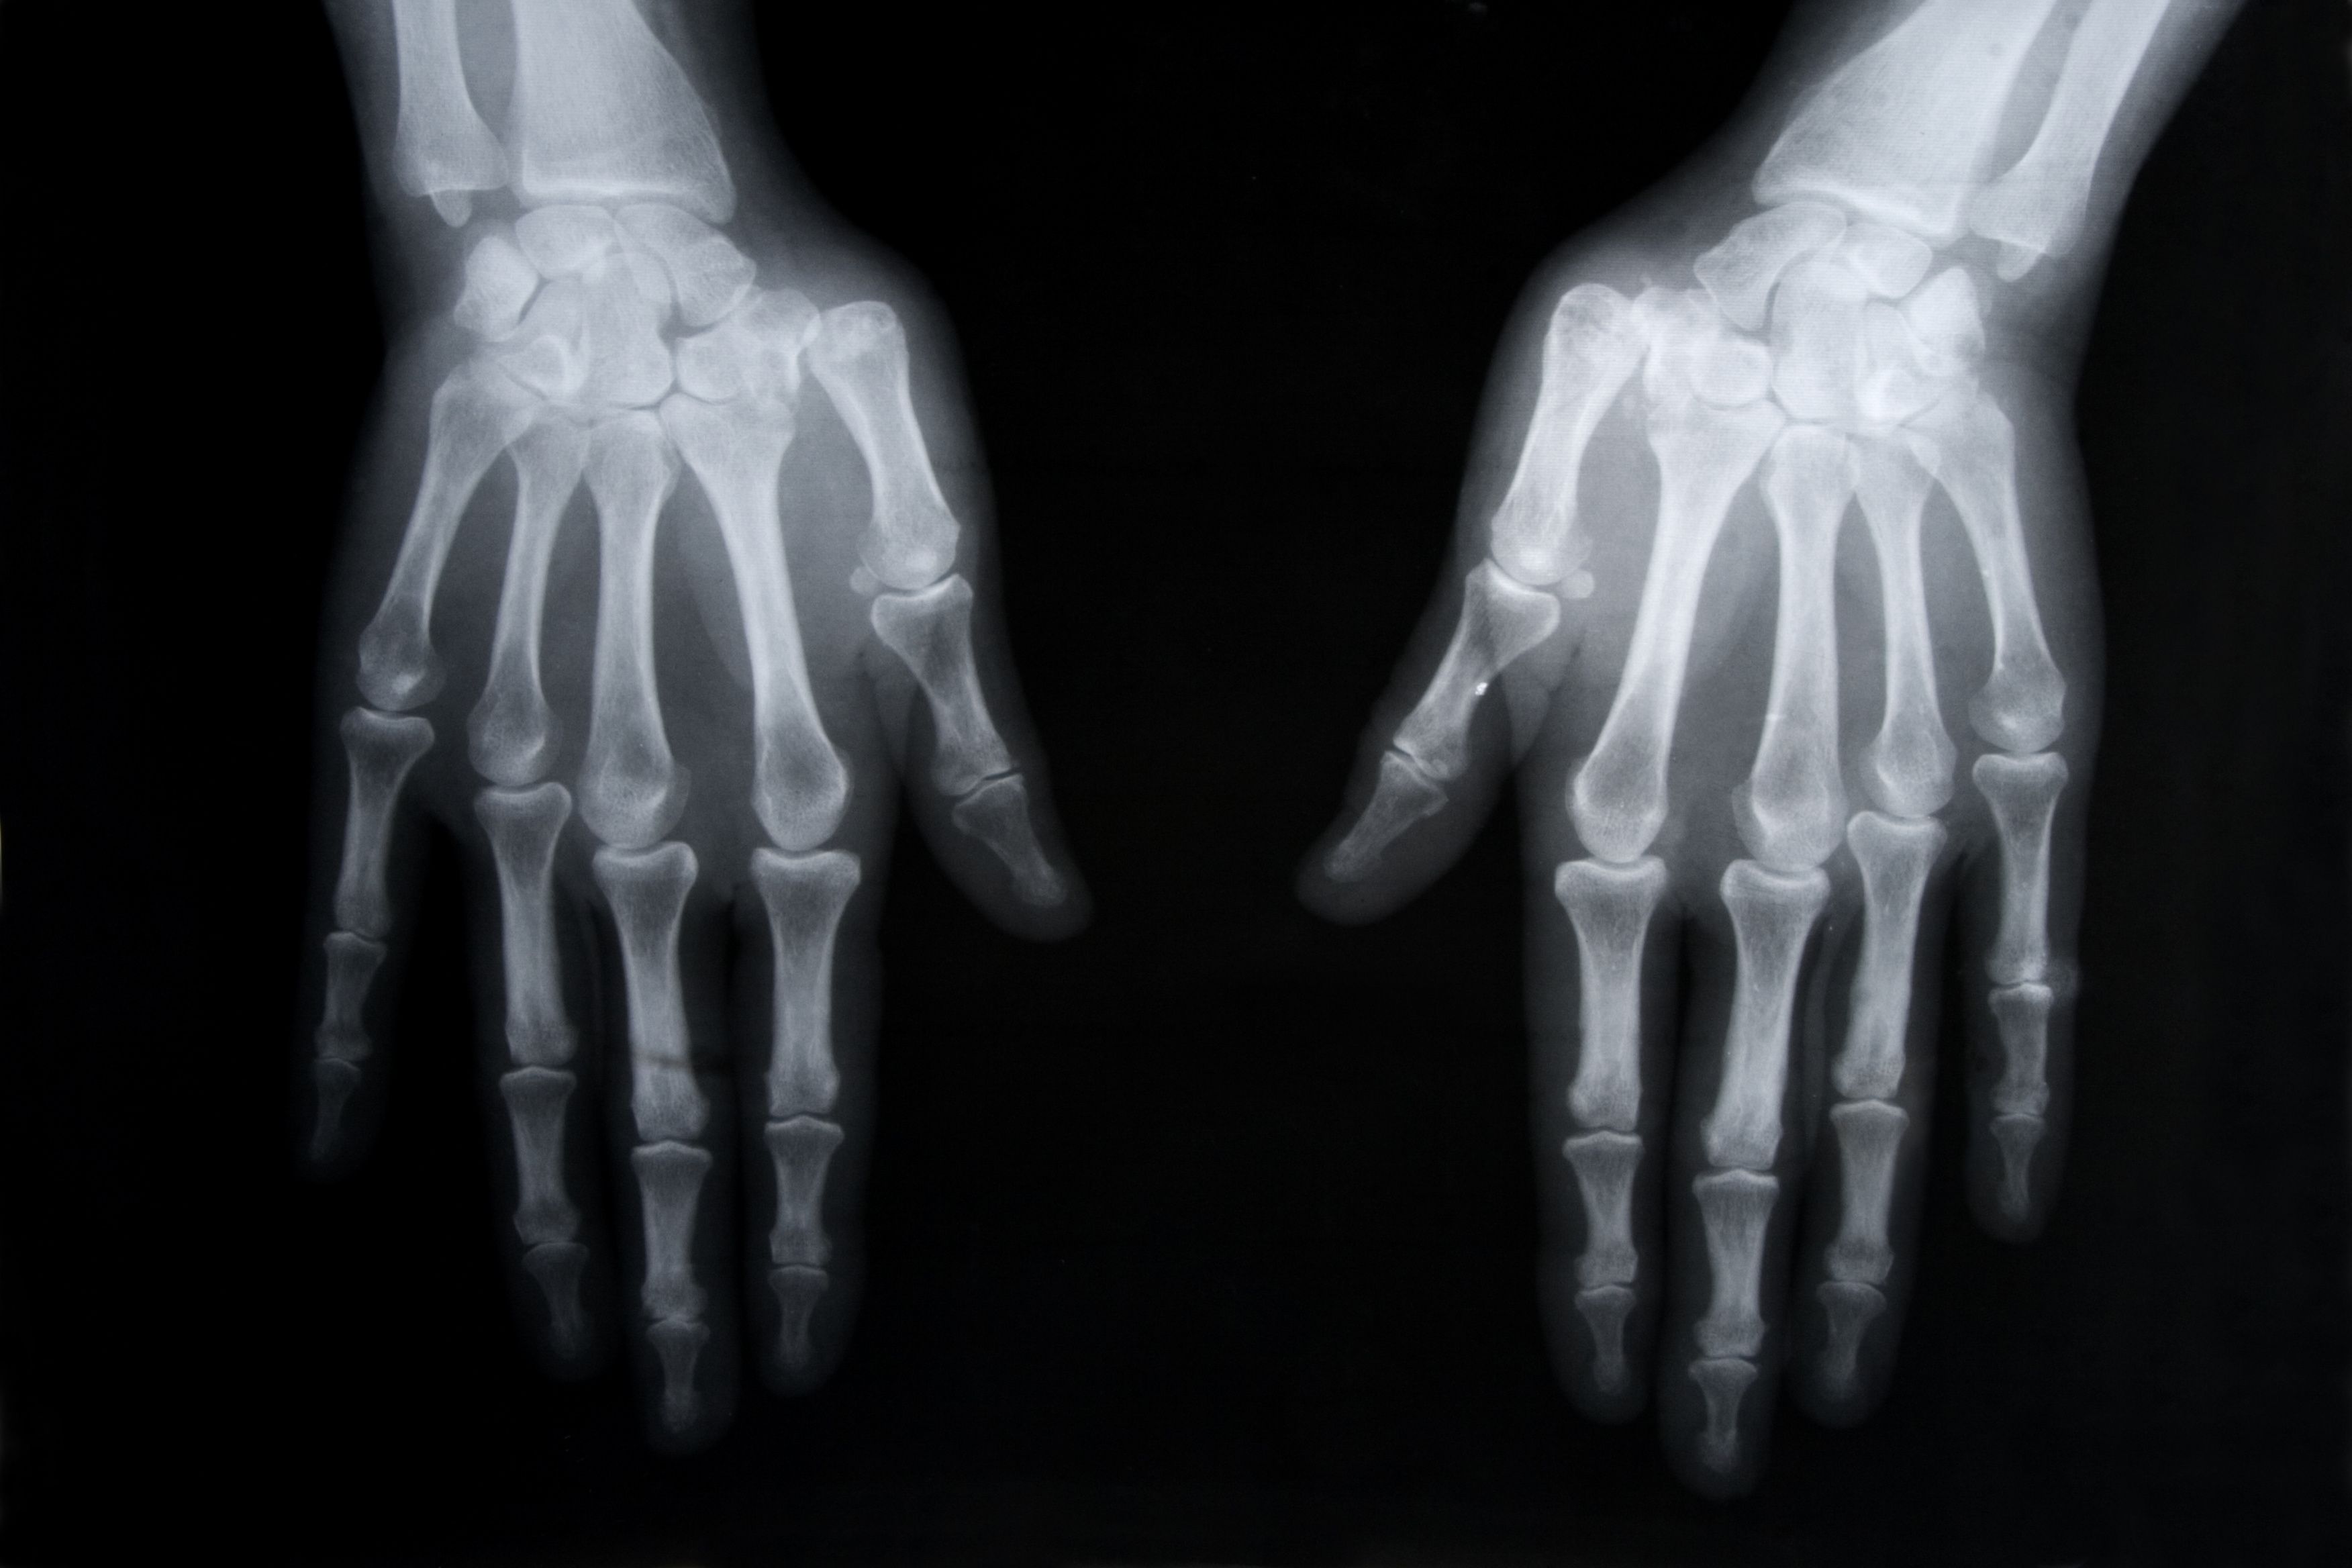

Early diagnosis and prompt effective management are important for the best outcomes in rheumatoid arthritis. Test your knowledge of how to achieve this with this quiz.

Treatment for rheumatoid arthritis has been associated with the development and worsening of some lung conditions. Test your knowledge with this quiz.

Patients with rheumatoid arthritis often have lung conditions. How much do you know about the risks of lung disease associated with rheumatoid arthritis? Test your knowledge with this quiz.